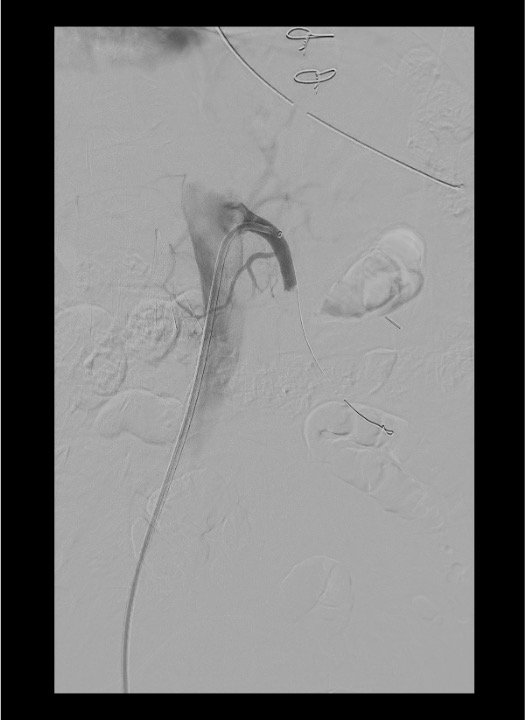

Lateral Aortogram